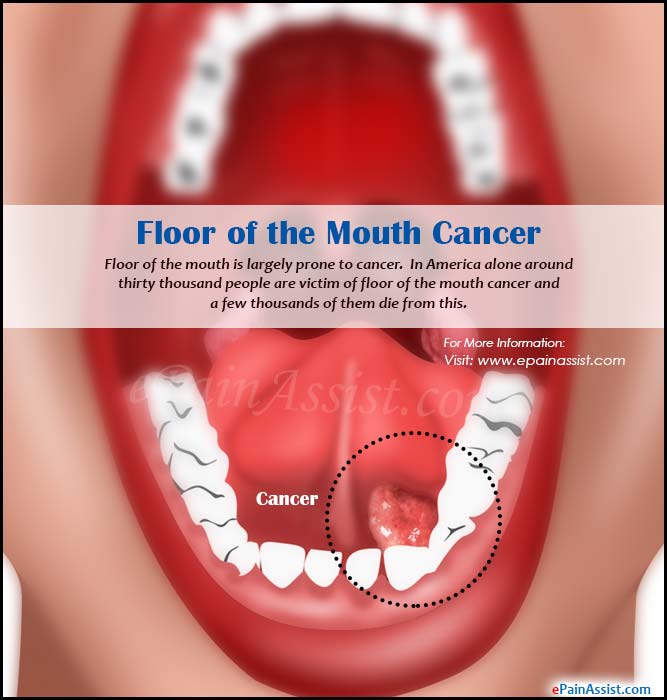

Floor Of The Mouth Cancer Japan Pdf Ppt Case Reports

Cancers Of The Floor Of The Mouth

Floor Of The Mouth Cancer

Floor Of The Mouth Cancer Causes Symptoms Treatment Survival

Malignant Tumors Of The Floor Of The Mouth Background

Cancers Of The Floor Of The Mouth

Cancers Of The Floor Of The Mouth